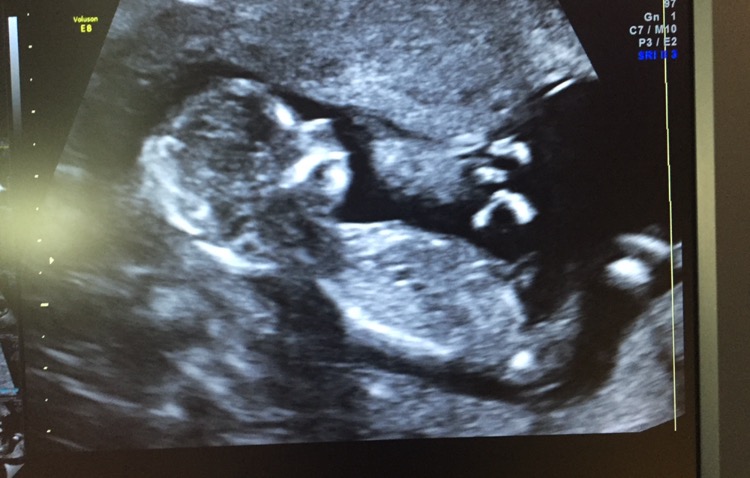

13 weeks 2 days NUB and skull guesses please

First of all, I know the shots are really bad. I have a really uncoperative baby combined with an anterior placenta which makes images less clear.

Anyway, the baby Measured 13 weeks 2 days and I wonder IF anyone is willing to try and guess either by nub or skull.

My doctor who performed the Scan gave a 95% girl guess despite unclear shot. He has 40 years experience in pregnancy ultrasounds and he correctly confirmed My sons gender at 11 week 5 Days a few years back.

I don't dare to trust IT.... Really hope for a girl. But From looking at it, the nub looks elevated to me. As in pointing upwards and therefor indicating boy.

At My 11 week 2 day NT scan he said IT was difficult but he had a girl lean already back then 2 weeks ago.

The nub was flat by then, but got mostly boy votes online due to "stacking".

Here I am asking Again, what do you guys think? Nub Theory? Skull theory?